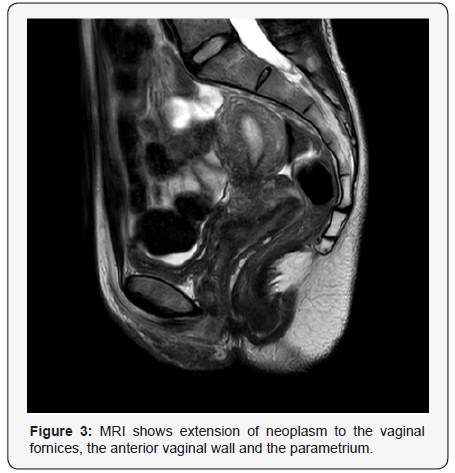

The sub epithelial region showed (Figure 2b) sheets of neoplastic lymphoid cells with irregular nuclear contours, vesicular nuclei, occasional prominent nucleoli and moderate amount of eosinophilic cytoplasm. Mitosis was frequent. Spindling of tumour cells was evident in areas. Immunohistochemical work up showed the tumour cells were positive for CD20 (Figure 2c) while negative for CD3, CD10, Bcl-6 and Cyclin D1. The neoplasm extended up to the deep resection margin. The final diagnosis was given as High grade squamous intraepithelial lesion (HSIL) (Cervical intraepithelial Neoplasia III/ CIN III) with Non-Hodgkin’s Lymphoma B-cell type; Diffuse Large B Cell (DLBCL) Further staging work up and imaging was done (Figure 3) which showed extension of neoplasm to the vaginal fornices, the anterior vaginal wall and the parametrium with involvement of the left ureteric wall and subsequent mild hydronephrosis.

CT neck, chest and abdomen showed no evidence of metastasis. In chest and abdomen; no significant abnormality noted. No significant lymphadenopathy or metastasis in chest. In abdomen, liver was displaying multiple hepatic focal lesions with progressive fill in the contrast likely hemangiomatous left hydroureteronephrosis, left ovarian cyst, retained fluid within the uterine cavity. PET CT scan impression came as hypermetabolic lesions involving the cervix with vaginal and parametrial involvement in keeping with biopsy proven metabolically active lymphoma. The remainder of the study shows no evidence of FDG avid lymphoma. Mild left hydronephrosis was noted. Since Lymphoma of cervix is a very uncommon lymphoma type and surgery has removed most of the disease, in the tumour board it was planned to consider chemotherapy followed by radiotherapy based on available data; measures that could be used in treating lymphoma of cervix. Different options of treatment was discussed and finally planned to give her 6 Cycles of R-CHOP followed by PET- CT and involved field Radiotherapy.